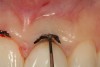

This patient presented with gingival recession above tooth No. 9 (Figure 1). Since this tooth had previous root canal therapy, the exposed root surface was dark and unesthetic. When comparing gingival zenith levels, the maxillary central incisors could be adjusted slightly in the apical direction so that they would be slightly higher than the lateral incisors. Also, the zenith above tooth No. 8 was slightly different in shape (flat) when compared to tooth No. 9. A thin tissue marker (Figure 2) was used to mark the tissue at the proposed corrected level and a photograph was taken to verify positions.

Figure 2  A tissue marker is used as a guide for the gingivectomy procedure to balance the gingival heights.

Figure 2